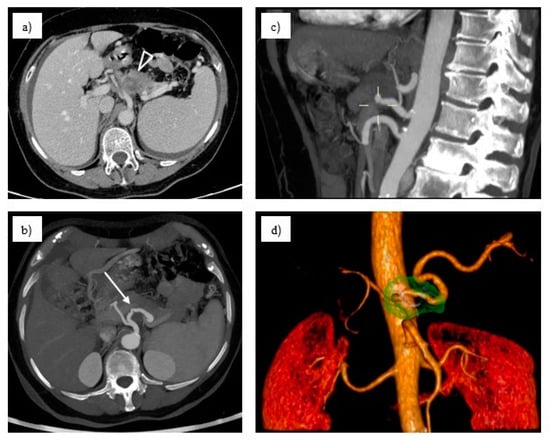

3.1. Imaging Examinations